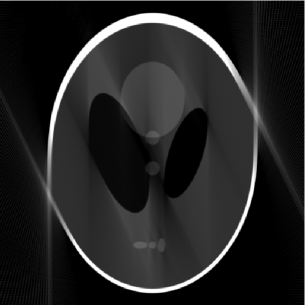

Figure 2: (a) 155155155 limited-angle projections in the 2-D frequency plane, (b) the full and outer-shell masks of the Shepp-Logan phantom, (c) FBP (PSNR=19.9PSNR19.9\mbox{PSNR}=19.9 dB), (d) DORE (PSNR=22.7PSNR22.7\mbox{PSNR}=22.7 dB), (e) GPSR (PSNR=22.9PSNR22.9\mbox{PSNR}=22.9 dB), (f) FPCASAS{}_{\footnotesize\mbox{AS}} (PSNR=22.5PSNR22.5\mbox{PSNR}=22.5 dB), (g) mask DORE (PSNR=25.8PSNR25.8\mbox{PSNR}=25.8 dB), (h) mask GPSR (PSNR=25.3PSNR25.3\mbox{PSNR}=25.3 dB), and (i) mask FPCASAS{}_{\footnotesize\mbox{AS}} (PSNR=26.4PSNR26.4\mbox{PSNR}=26.4 dB) reconstructions.

Shepp-Logan phantom reconstruction. We simulated limited-angle parallel-beam projections of an analog Shepp-Logan phantom with 1superscript11^{\circ} spacing between projections and missing angle span of 25superscript2525^{\circ}. Each projection is computed from its analytical sinogram using [8, function ellipse_sino.m] and [7] and then sampled by a receiver array containing 511511511 elements. We then compute FFT of each projection, yielding N=512𝑁512N=512 frequency-domain measurements; the corresponding frequency-domain sampling pattern is shown in Fig. 2.

Fig. 2 depicts both the full and outer-shell masks of the phantom that we use to implement the DORE, GPSR, FPCASAS{}_{\footnotesize\mbox{AS}} and mask DORE, GPSR, and FPCASAS{}_{\footnotesize\mbox{AS}} methods, respectively. Because of the nature of X-ray CT measurements, our full mask has circular shape containing p=205859𝑝205859p=205859 signal elements. The elliptical outer-shell mask containing pM=1308150.6355psubscript𝑝M1308150.6355𝑝p_{{\scriptstyle{\rm M}}}=130815\approx 0.6355\,p pixels has been constructed from the phantom’s sinogram using k=1180Aπ(k1)/180superscriptsubscript𝑘1180subscript𝐴𝜋𝑘1180\bigcap_{k=1}^{180}A_{\pi\,(k-1)/180}, see Section V; this choice of the mask implies that we have prior information about the shape of the outer shell of the Shepp-Logan phantom beyond the information available from the limited-angle projections that we use for reconstruction, see Fig. 2.

Figs. 22 show the reconstructions of various methods. To facilitate comparison, we employ the common gray scale to represent the pixel values within the images in Figs. 22. Clearly, taking the object’s contour into account improves the signal reconstruction performance.